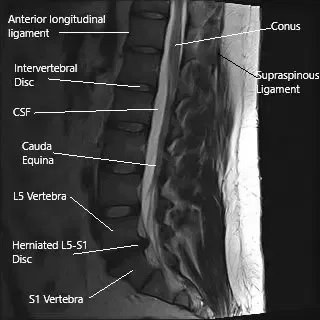

MRI of the lumbar spine in sagittal section showing herniated L5-S1 intervertebral disc.

The spine consists of vertebrae separated by intervertebral discs, which cushion and stabilize the spine. The nerve roots exit the spinal cord through the intervertebral foramen. The lumbar spine, in particular, is prone to disc herniation due to its weight-bearing function. The sciatic nerve, originating from the lumbar and sacral spinal roots, runs through the pelvis and down the legs, providing motor and sensory function.

Diagnosis is typically clinical, based on a patient’s history and physical examination. Imaging tests like MRI are crucial for identifying disc herniations, degenerative changes, and other structural abnormalities in the lumbar spine. MRI scans in sagittal and axial views provide detailed images of the disc space, nerve roots, and the surrounding structures, helping guide treatment decisions.